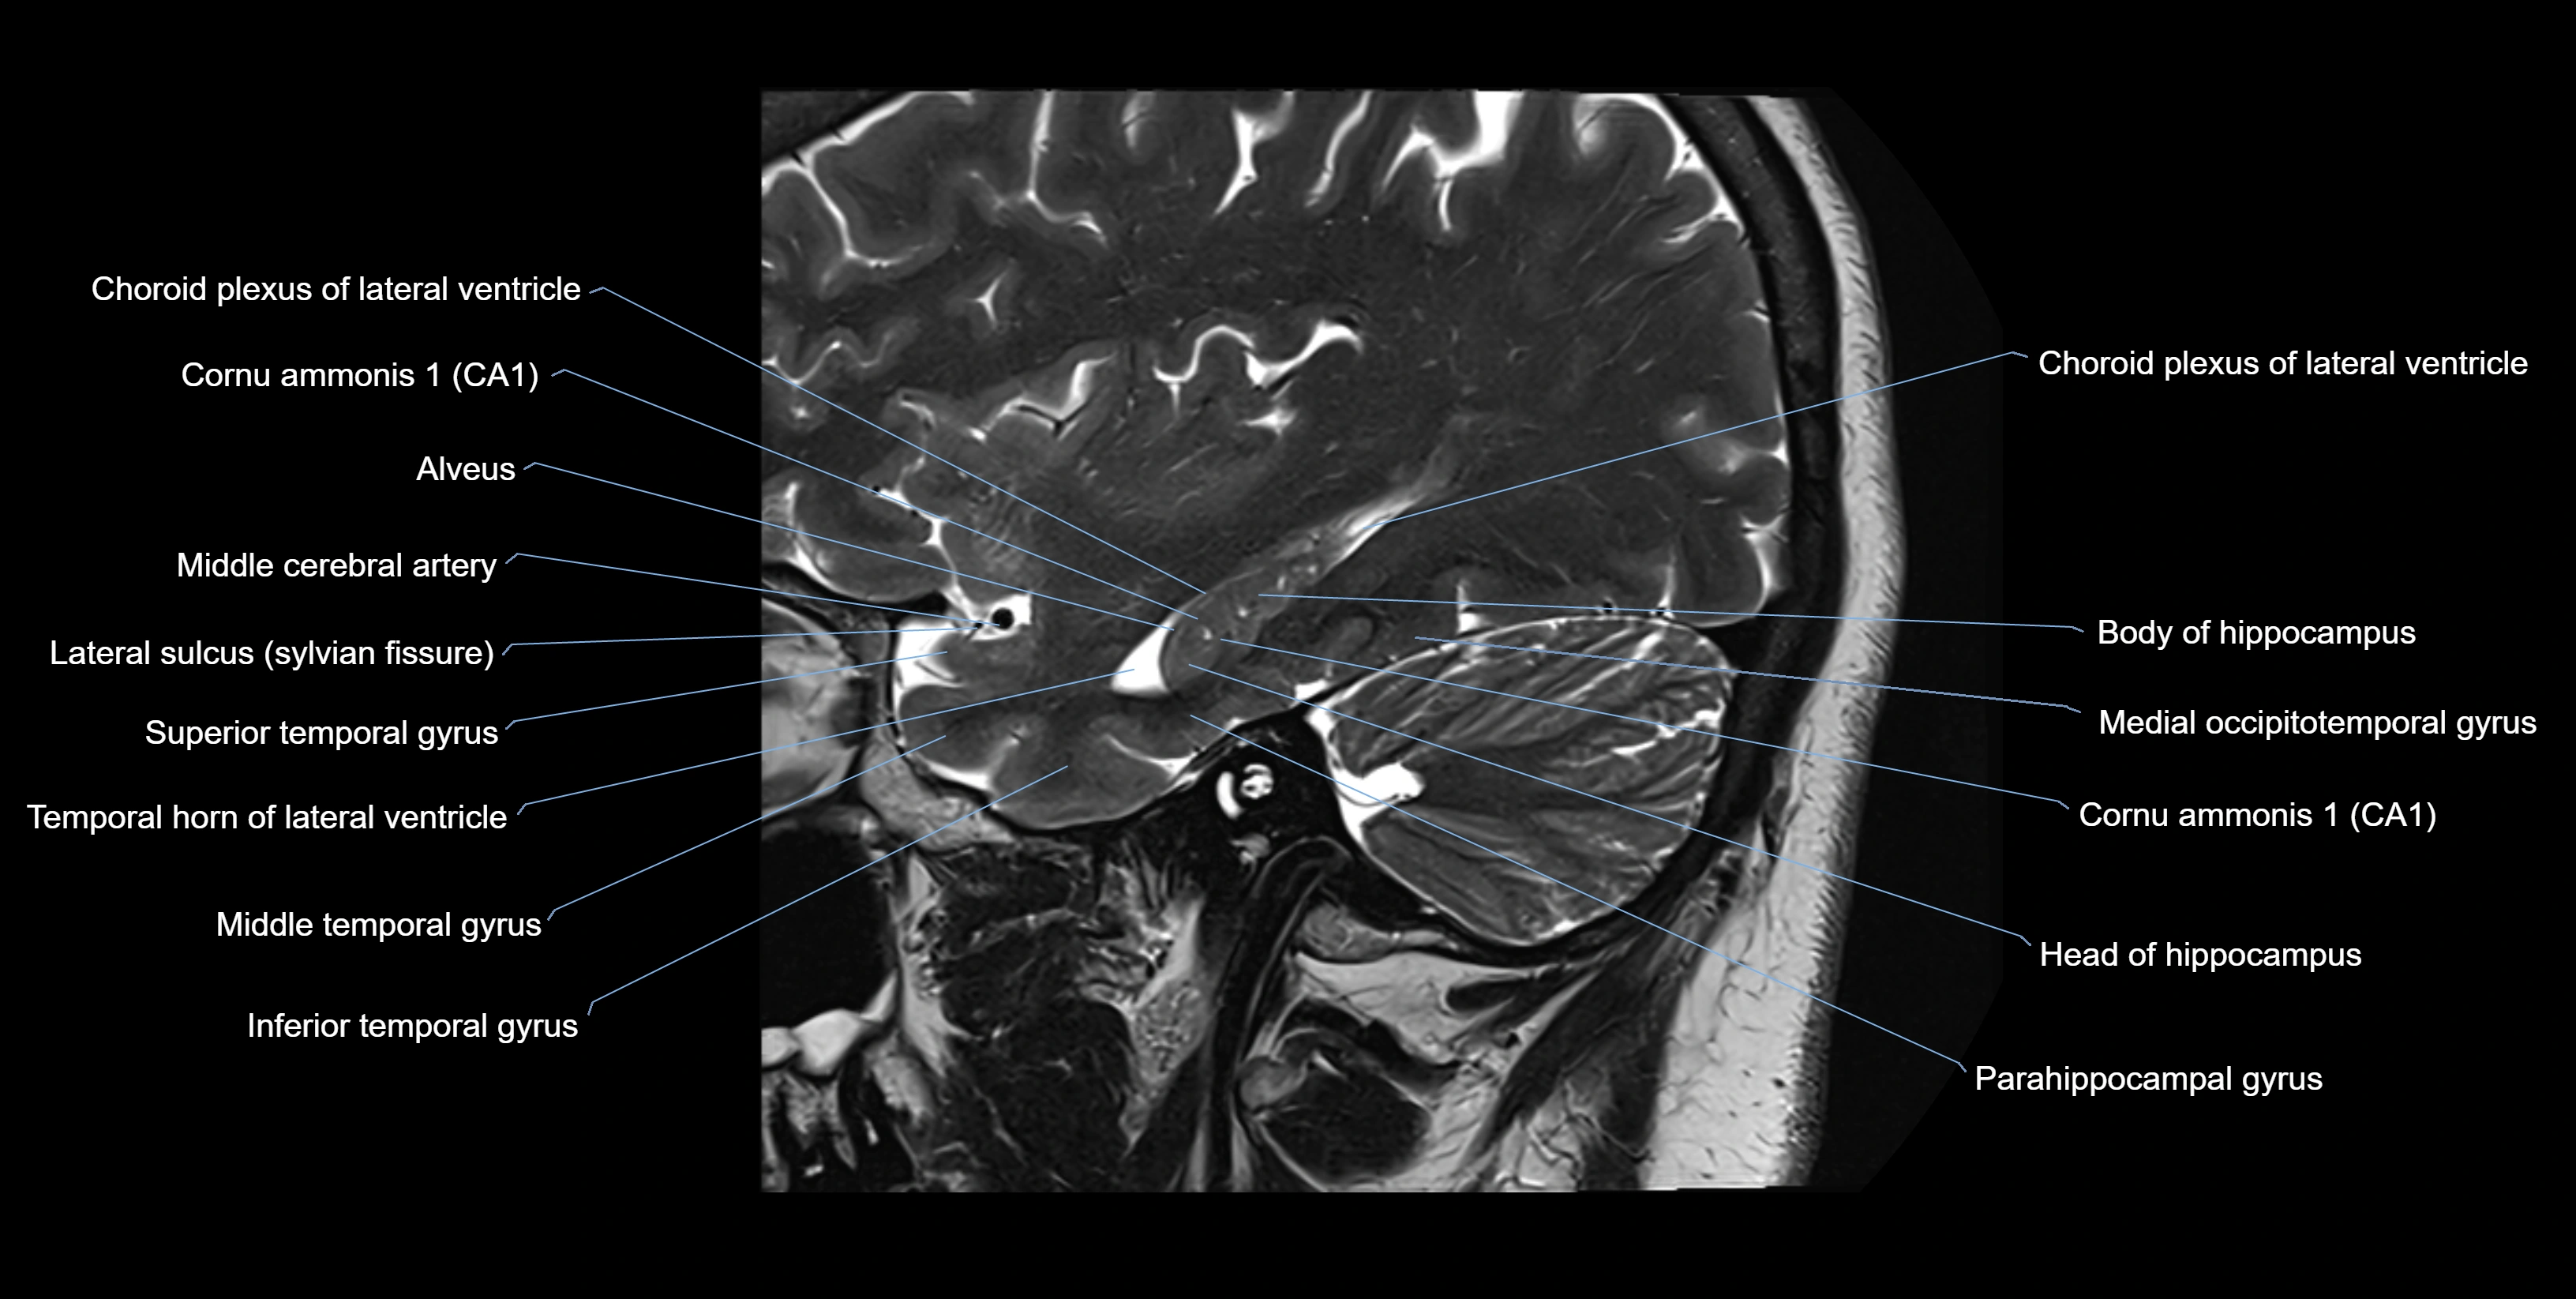

The alveus of the hippocampus is a thin, white matter layer covering the superior (ventricular) surface of the hippocampus within the temporal horn of the lateral ventricle. It consists of myelinated efferent fibers arising primarily from the pyramidal neurons of the hippocampus. These fibers converge medially to form the fimbria of the hippocampus, which continues posteriorly into the fornix, forming a crucial part of the Papez circuit involved in memory consolidation and emotional processing.

The alveus serves as the initial output pathway of the hippocampal formation, linking it to other limbic structures including the hypothalamus, mammillary bodies, and cingulate gyrus. Because of its intimate relationship with the hippocampal head and tail, it is often evaluated in cases of temporal lobe epilepsy, hippocampal sclerosis, and neurodegenerative diseases.

Location and Structure

• Position: Lies on the ventricular (superior) surface of the hippocampus, beneath the ependyma of the inferior horn of the lateral ventricle.

• Composition: A thin sheet of myelinated axons derived mainly from hippocampal pyramidal cells.

• Course: Fibers run medially along the hippocampal surface to form the fimbria of the hippocampus, which curves upward and backward into the fornix.

• Relations:

• Superiorly: Ependyma and CSF of the temporal horn of the lateral ventricle

• Inferiorly: Pyramidal cell layer of the hippocampus (CA1 region)

• Medially: Fimbria and fornix

• Laterally: Temporal lobe white matter and parahippocampal gyrus

MRI Appearance

T2-weighted images:

• Alveus: Low signal line overlying brighter hippocampal gray matter.

• CSF: Bright hyperintense.